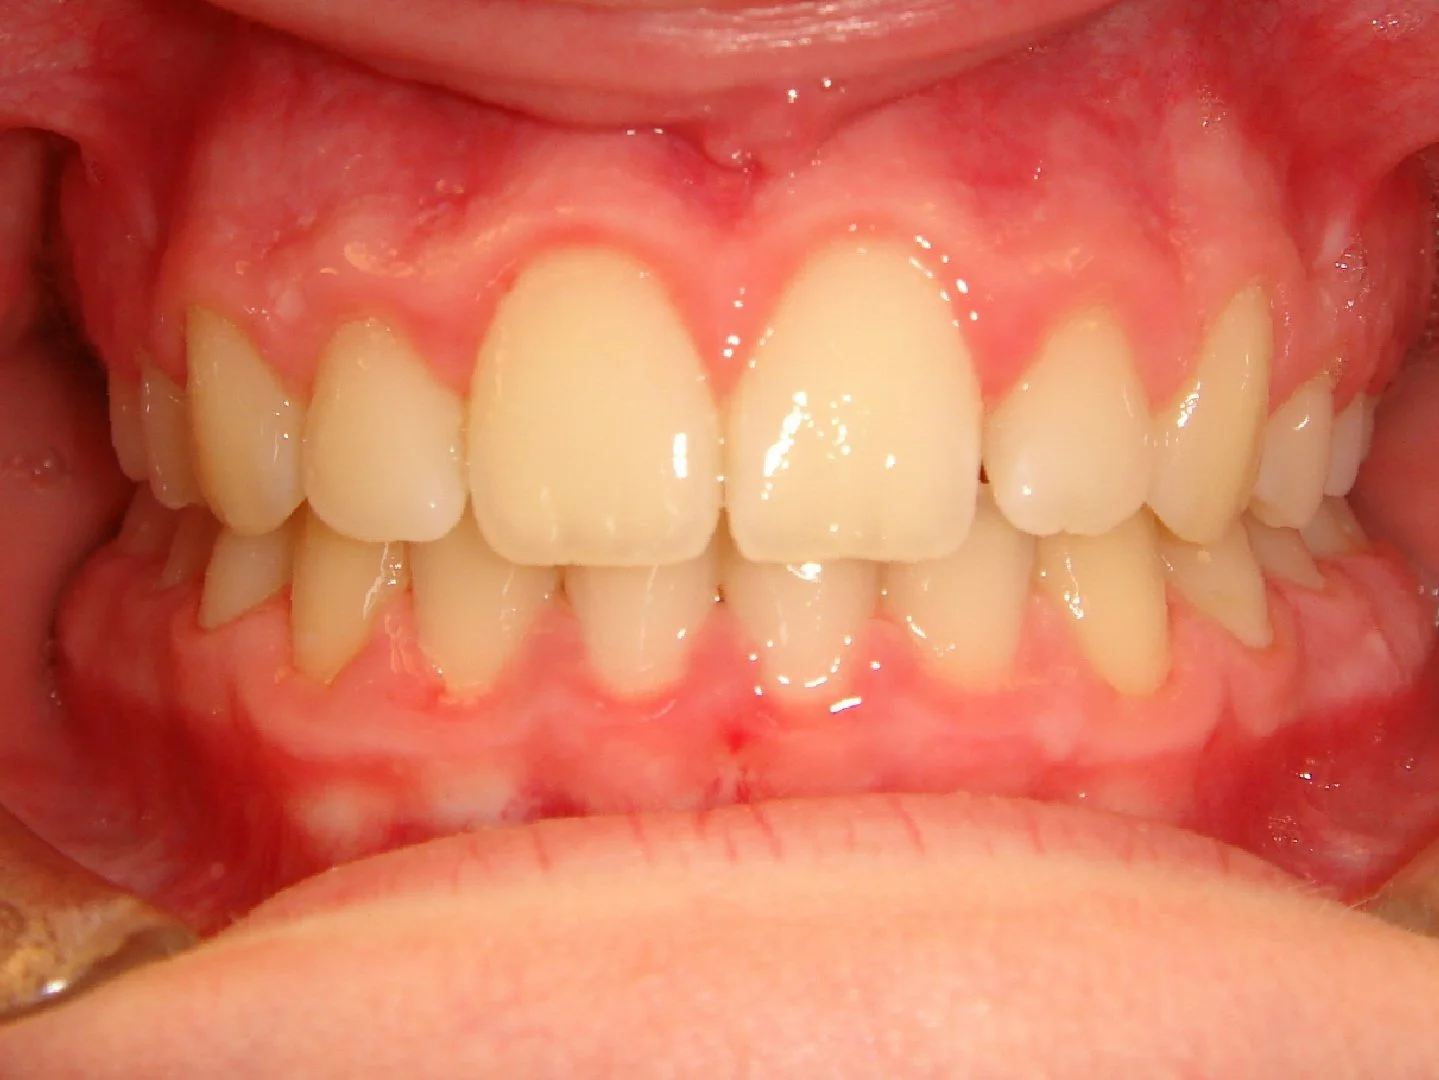

Case #1: Excess Overjet / Overbite & Crowding

Before

This 10 year old girl had crowding of her upper and lower teeth, and an extreme overjet and overbite. Her case was treated over 2 years with braces and elastics.